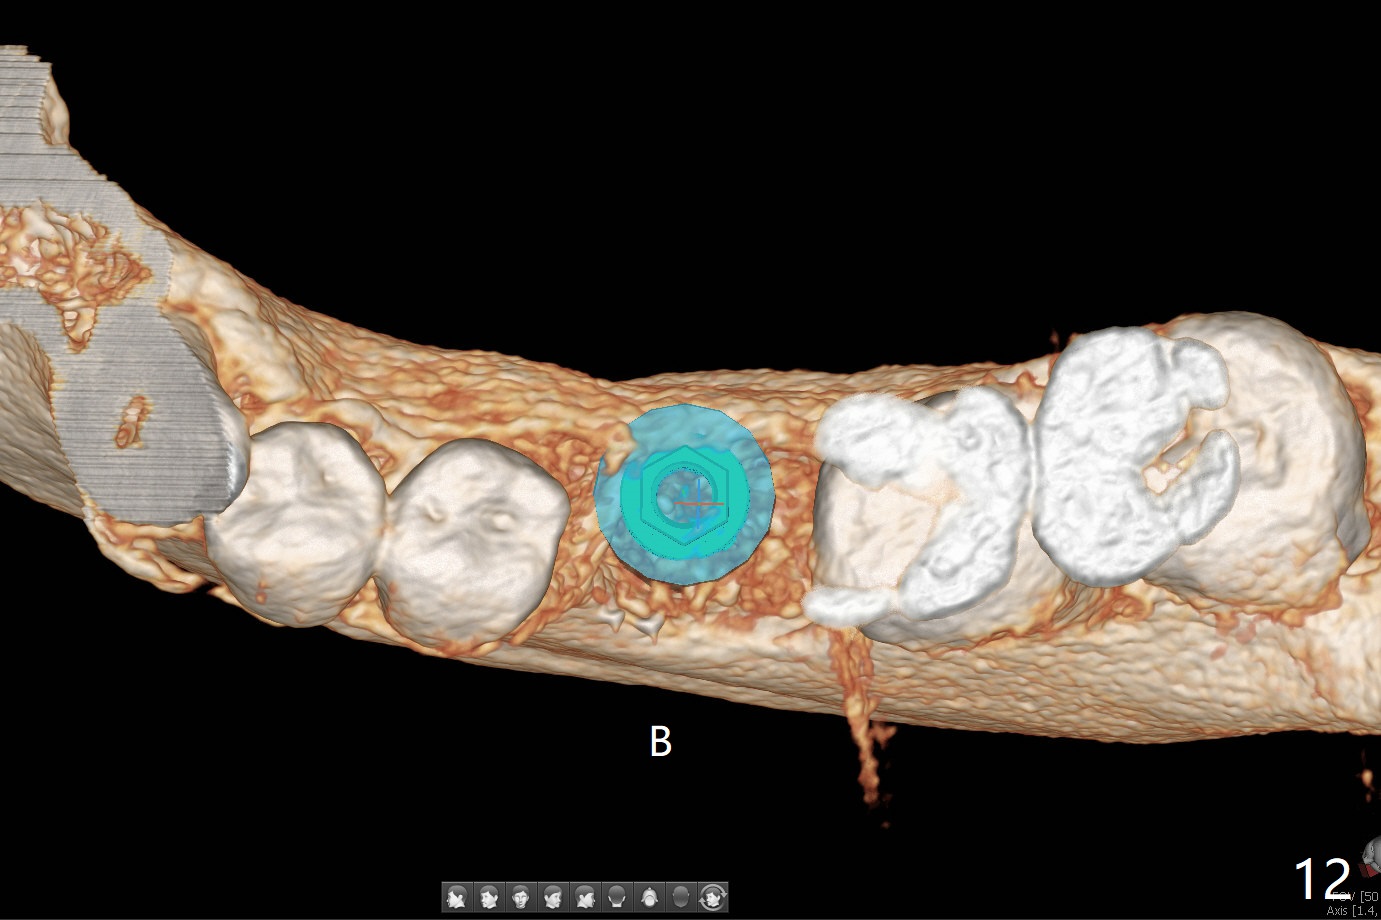

Extraction of the tooth #19 with large PARL (Fig.1,2) confirms the loss of buccal plate, but the crestal bone exists. After failure to place an implant in the middle socket with removal of the lingual septal bone, socket preservation is done with PRF and sticky bone (Fig.3). There is possibility to place a ~4 mm implant in the mesial socket (Fig.4). Or just drop a 5x11 mm Bicon Implant into the large socket, surrounded by sticky bone. When periodontal dressing is removed 18 days postop, the bone graft seems to remain to be "sticky" yellowish, while the granulation tissue has started to grow into the center of the socket from the previously buccal and lingual furcae (Fig.5 reddish). Granulation tissue seems to cover the bone graft (Fig.6), although there is smells when the periodontal dressing is removed. Bone height reduces nearly 3 months postop (Fig.7). The buccal plate collapses (Fig.8), but there seems no further bone loss 4 months postop (Fig.9). Because of buccal plate loss, an implant will be placed lingually with guide (Fig.10-12 green). Bone graft may be placed buccally after implant placement with probing.